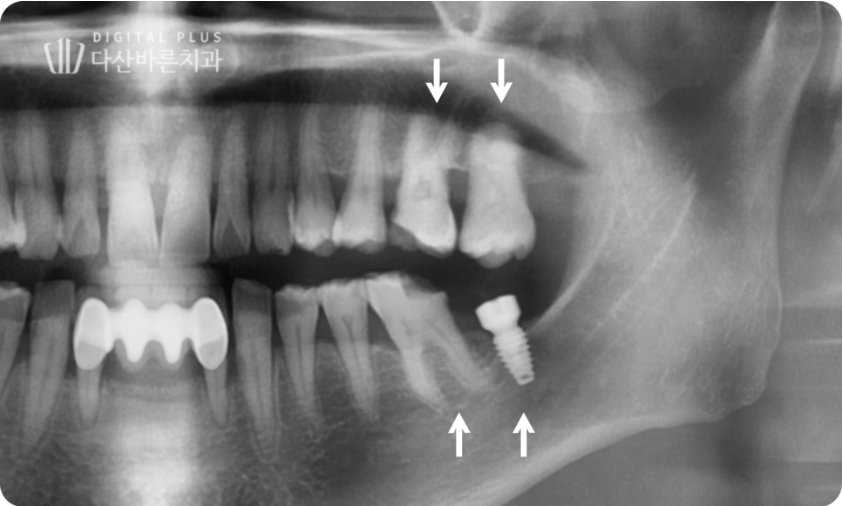

우선 위쪽 대합치의 추가적인 정출을 방지하기 위해,

빠진 치아 자리를 대체할 수 있는 임플란트 치료를 먼저 진행합니다.

▲ 위 어금니 추가적인 치아 정출을 방지하기 위해, 아래쪽 빠진 치아 임플란트 치료 먼저 진행.